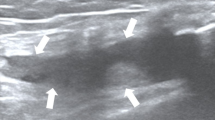

a Photograph of the tensile testing platform. Resistance changes of b Au temperature sensor and c PEDOT humidity sensor caused by repeated tensile deformation. d Output temperature of Au heater is recorded by an infrared (IR) camera. e, f Comparison of output temperature fluctuations with (red line) and without (blue line) close-loop control. Resistance changes of sensors during g walking and h running. i Long-term stability of MSU

In addition, the influence of human motion on our system was investigated. Figure 3g, h demonstrates the relative resistance change of the temperature sensor and humidity sensor during walking (the speed is ~3 km/h) and running (the speed is ~7 km/h), respectively. The system was fixed on the joint of the participants by transparent medical tape (Fig. S4), and an accelerometer (MPU6050, TDK InvenSense, USA) was integrated onto the FPCB to monitor the movement of knee joints. It is noted that periodic fluctuations are recorded by the humidity and temperature sensors. The fluctuations match the signals recorded by the accelerometer, which reflects the step frequency of walking or running. Although the motion of humans can induce notable fluctuations in the sensors, the accurate humidity and temperature can be obtained by calculating the average as indicated by the dashed lines in Fig. 3g, h. The humidity is almost constant when the participant is walking, while it shows a slight increase when running. On the other hand, the temperature increases 0.34 °C and 0.59 °C when walking and running, respectively. Considering the temperature rise and sweating caused by exercise, the on-body test results are reasonable. Furthermore, to evaluate the long-term stability of our stretchable device, the electrical resistance of MSU was recorded after daily testing. As shown in Fig. 3i, the electrical resistance of both sensors and the heater remains nearly constant during the test. The consistency results are comparable to the studies reported in other literatures44,47,53.